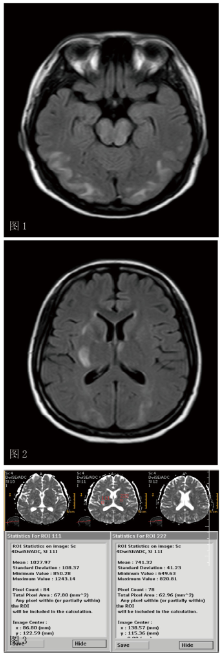

诊断考虑:头晕呕吐后四肢抽搐查因:可逆性脑后部白质病变? 静脉窦血栓形成?。进一步完善MR+增强+MRV检查,结果提示:

1、双侧额顶枕叶、桥脑及中脑、左侧小脑半球、双侧基底节区及右侧侧脑室旁,左侧放射冠区多发病变,结合病史,考虑可逆性后部白质脑病综合症,建议治疗后复查;

2、MRV检查示未见异常。经过影像科专家及上级医生会诊,考虑诊断为可逆性脑后部白质病变,给予激素冲击治疗,患者症状迅速控制,1天后患者血压稳定,未诉出现头痛头昏,恶心呕吐,未出现四肢抽搐,3天后痊愈出院。